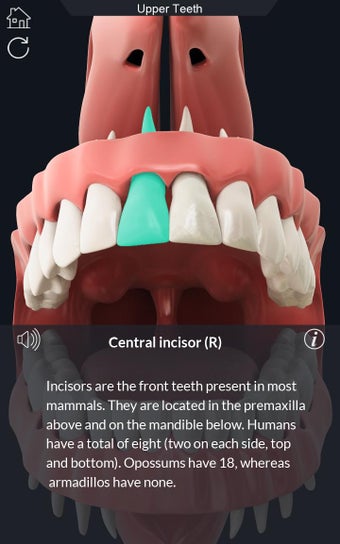

Esta aplicación es un modelo 3D de los dientes, que contiene muchas partes y muestra las condiciones dentales. Cada parte tiene un nombre y una función. Puedes mover la cámara alrededor del modelo para obtener una vista de 360° de las diferentes partes. Puedes hacer zoom para ver mejor cada parte. También puedes rotar la cámara para obtener una vista diferente del modelo.